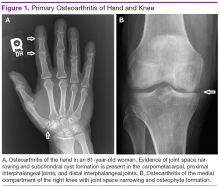

Plain radiographs are extremely helpful in denoting the extent of OA in a particular joint. Radiographic features of OA include narrowing of the joint space, osteophyte formation, and subchondral bone abnormalities. Narrowing of the joint space and alignment abnormalities occur due to loss of articular cartilage. Changes in the subchondral bone include sclerosis and cystic lesions. Erosive changes, ankylosis, and calcification of the articular cartilage are typically absent.

In the hands, a particular pattern is noted involving the PIP and DIP joints with characteristic sparing of the MCPs (Figure 1A). The first CMC joint is also commonly involved, with bony osteophyte formation and joint space loss. In the knee and hip, loss of joint space with subchondral bone cyst and osteophyte formation is common (Figure 1B).